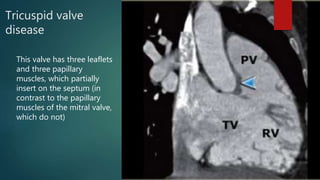

Tricuspid valve

disease

This valve has three leaflets

and three papillary

muscles, which partially

insert on the septum (in

contrast to the papillary

muscles of the mitral valve,

which do not)